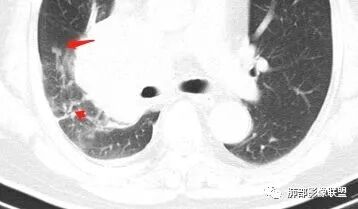

局限性中央间质增厚,考虑癌性淋巴管炎

部分区域有结节感

Coke with ice: 这个是标记的结节感吗?

南边: 奇怪,你们都不觉得这里有结节?

了: 气腔结节

毛勤香: 这个人有癌淋,有点结节感

Coke with ice: 嗯,不明显的结节感可以考虑用MPR和薄层结合起来看,会不会判断的更准一些

2.右肺小叶间隔增厚伴微小结节,提示癌性淋巴管炎。